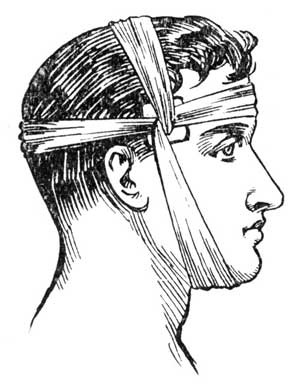

Where it appeared to be useful, illustrations have been introduced, which may help those to whom the treatment is quite new, to practice it more easily and correctly, and to understand better the theories on which it is founded.